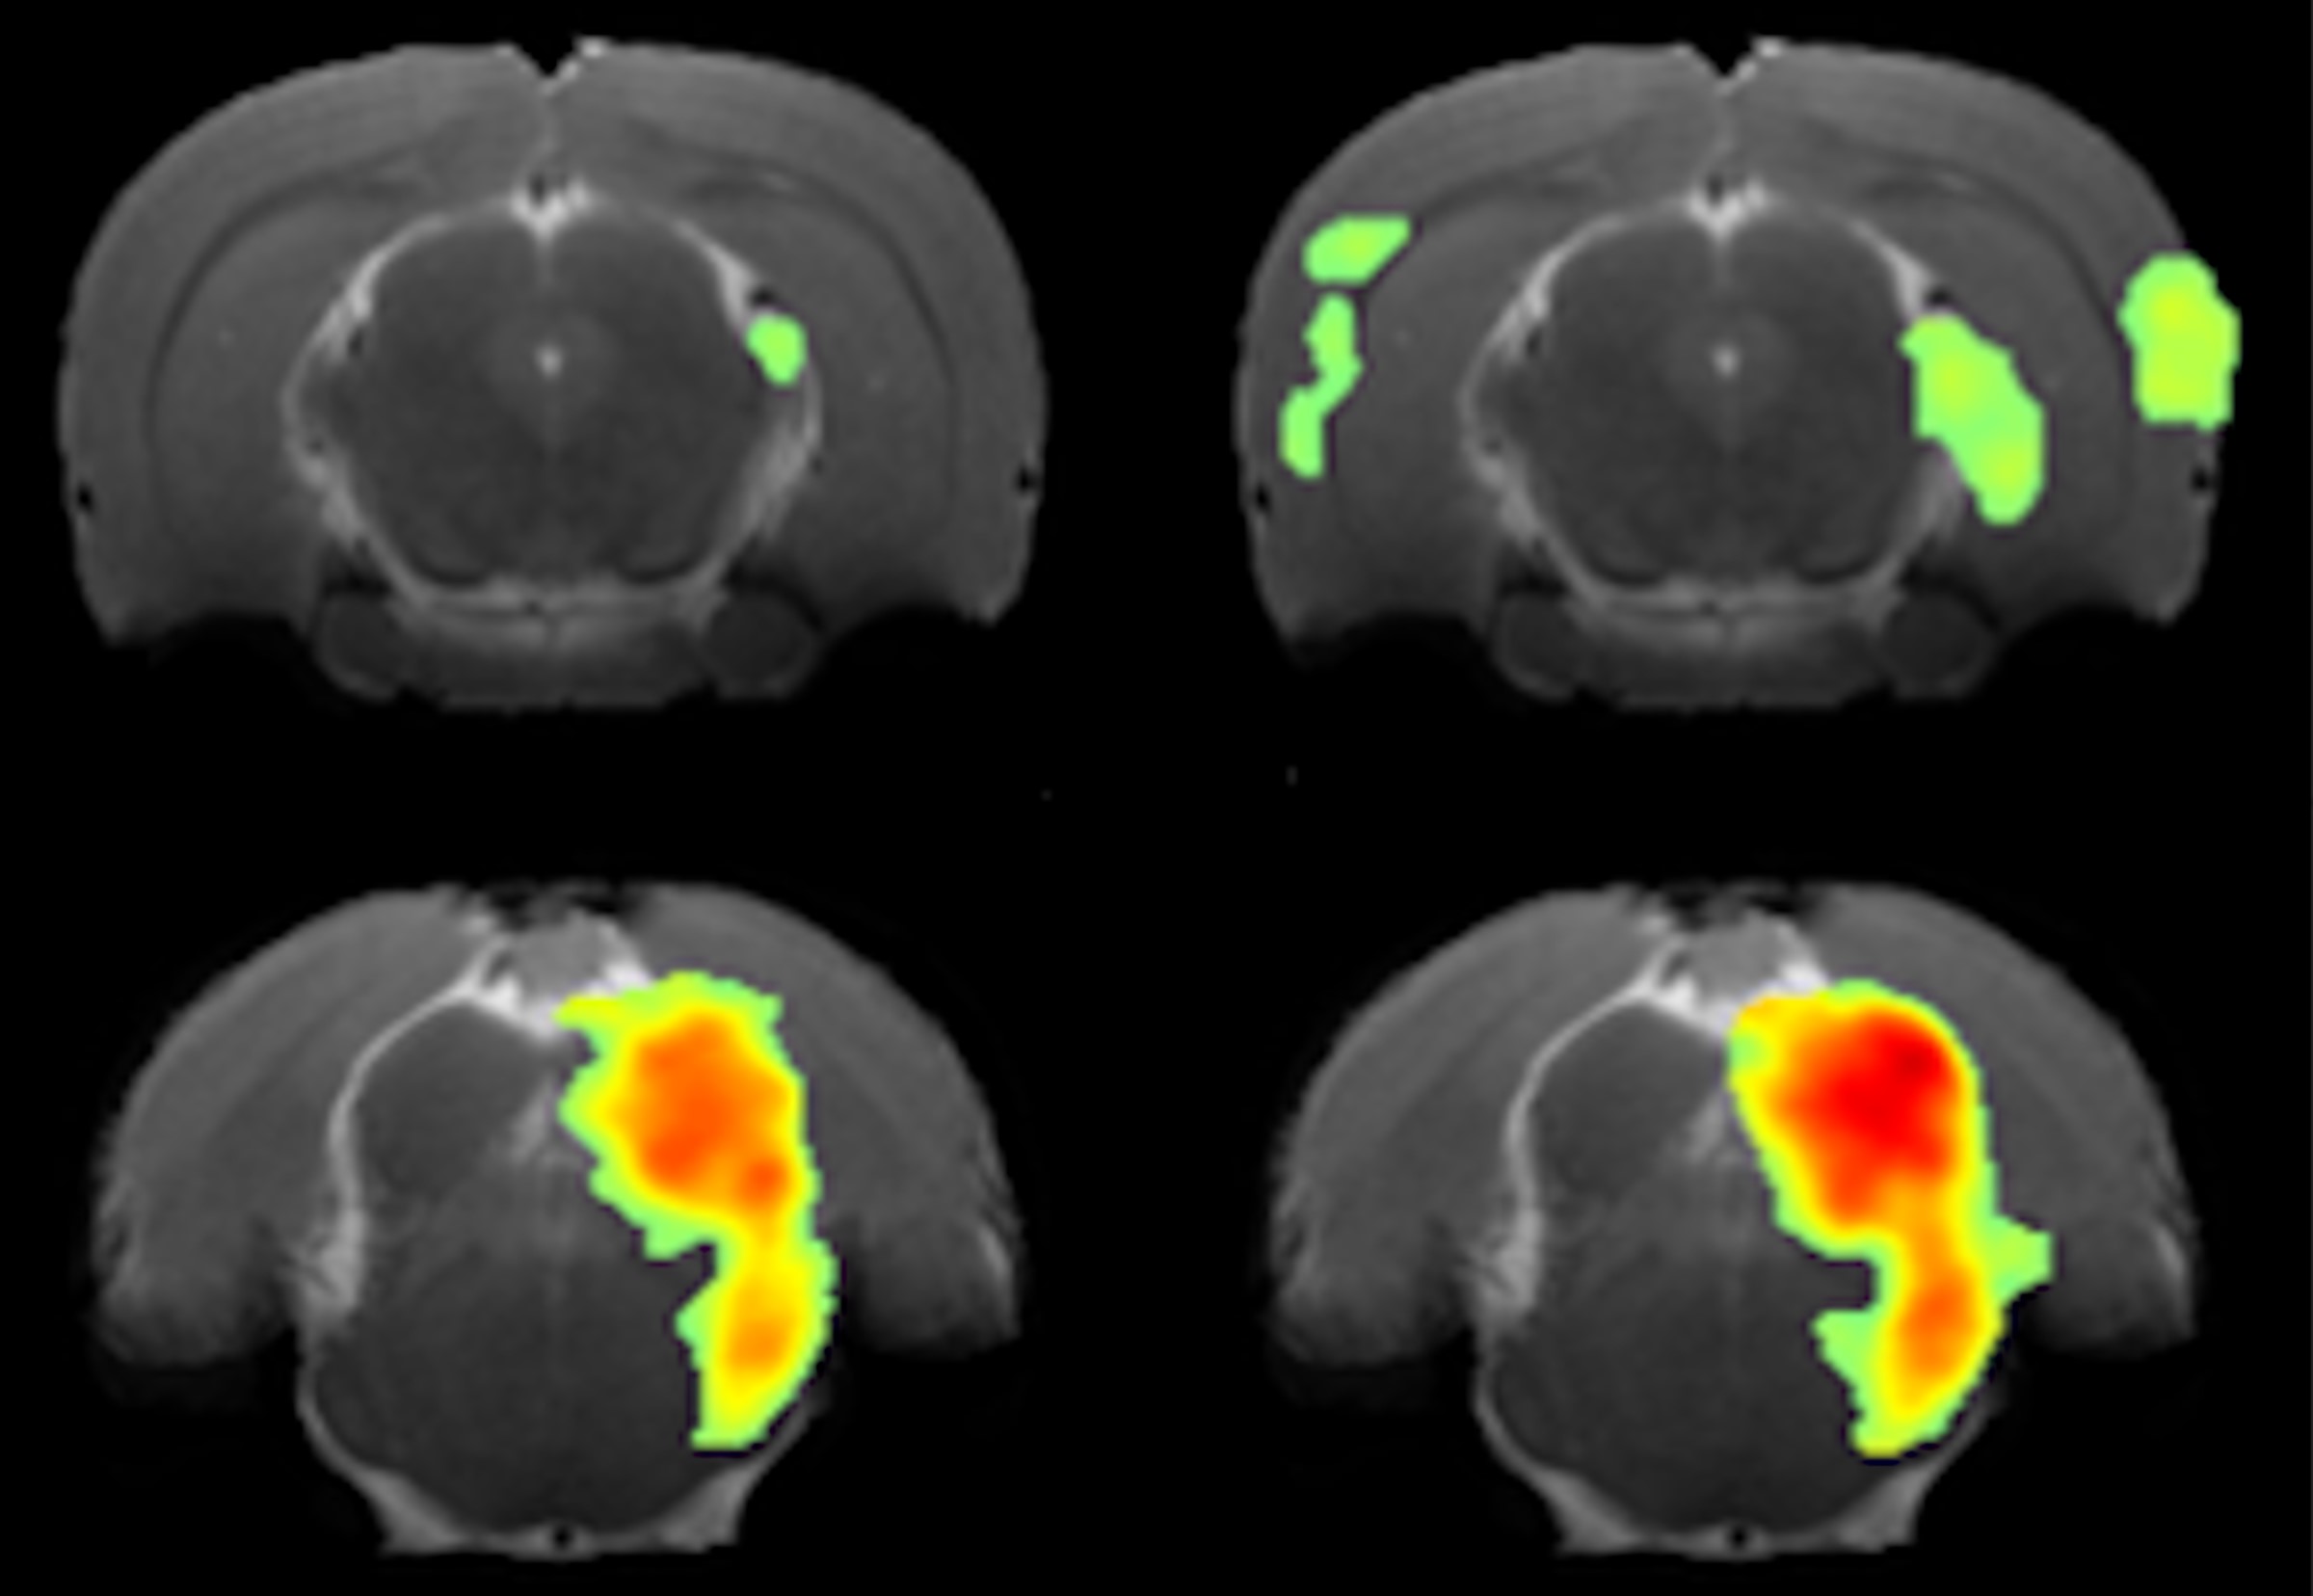

Functional magnetic resonance imaging of enhanced central auditory gain and electrophysiological correlates in a behavioral model of hyperacusis

Hyperacusis is a debilitating hearing condition in which normal everyday sounds are perceived as exceedingly loud, annoying, aversive or even painful. The prevalence of hyperacusis approaches 10%, making it an important, but understudied medical condition. In this work, we develop functional magnetic resonance imaging (fMRI) for studying hyperacusis in a behaviorally verified rat model. Pairing animal disease models with novel methodology is extremely valuable for understanding the basic mechanisms of the disease, aiding in future prevention and treatment. We observed significant neural hyperactivity in response to sound in the brain cortex, but less in lower regions such as the brainstem. This work will also help bridge basic understanding acquired from animal models with clinical observations in human patients as fMRI is performed on both.